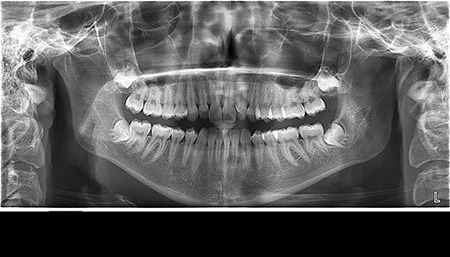

- Цифрова панорамна рентгенографія (ортопантомограма) – дає цілісне зображення всієї щелепно-лицевої системи.

Цифрова панорама Полтава: широкий погляд на здоров’я порожнини рота

Що ви уявляєте, коли лікар говорить про ортопантомограму? Насправді, це знімок усієї зубощелепної системи, який охоплює обидві щелепи, гайморові пазухи та скронево-нижньощелепні суглоби. Таке оглядове фото дозволяє стоматологу отримати загальне уявлення про стан зубів, кісткових структур та навколишніх тканин.

Ортопантомограма Полтава є незамінною при первинній діагностиці, коли потрібно оцінити загальний стан ротової порожнини. Її призначають у наступних випадках:

- для виявлення прихованих каріозних уражень;

- для оцінки стану пародонту (ясен і кістки);

- перед ортодонтичним лікуванням;

- перед видаленням зубів мудрості;

- для моніторингу росту та прорізування зубів у дітей.

Цифрова панорама Полтава успішно використовується для первинної діагностики в момент першого звернення до лікаря, бо дозволяє виявити всі патологічні процеси в зубах, кістці, навколощелепних тканинах. Завдяки їй лікар не припуститься помилок під час планування й виконання складних ортопедичних робіт.

Діагностика зубів Полтава із застосуванням ортопантомограми має ряд переваг:

- швидке та безболісне обстеження (триває всього кілька хвилин);

- мінімальна доза опромінення – робить процедуру безпечною навіть для дітей;

- загальний огляд усієї порожнини рота на одному знімку – максимальна інформативність для стоматолога;

- можливість зберігання знімків у цифровому форматі для подальшого порівняння та динаміки лікування.